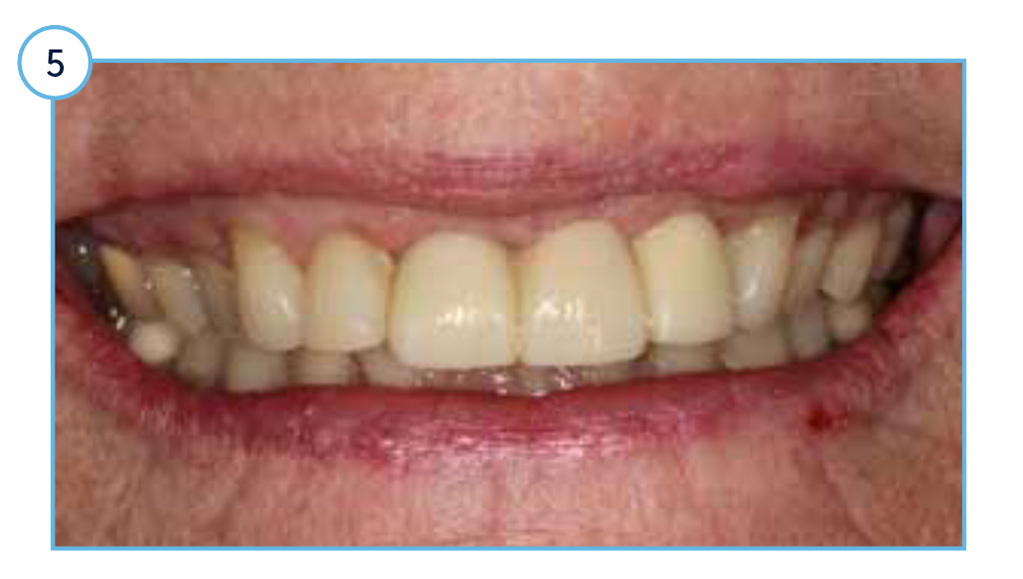

Preoperative clinical view of the incisor extraction sockets.

Clinical view of the aesthetic outcome one-year post restoration.